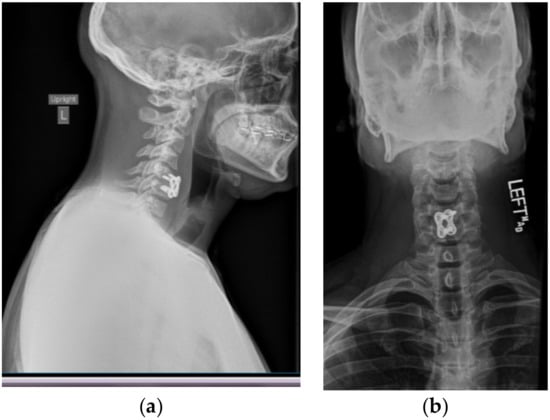

A postoperative CT scan confirmed the proper anterior fixation of the plate screws, interbody device, and bone graft placement following the patient’s discectomy and arthrodesis (Figure 2). Postoperative anterior and lateral X-rays (Figure 3b,a respectively) were also obtained in order to visualize and confirm proper placement of the anterior cervical plate and evaluation of alignment.

Figure 3. Postoperative X-ray showing postsurgical changes related to anterior fusion at C5–C6, with interval decrease in prevertebral soft tissue swelling. C1–C7 are visualized on the lateral view (Figure 3a) for evaluation of alignment. There is straightening of the normal cervical lordosis. Alignment is otherwise grossly unremarkable when allowing for patient rotation. Anterior instrumentation is noted at C5–C6 on both lateral and anterior (Figure 3b) views.